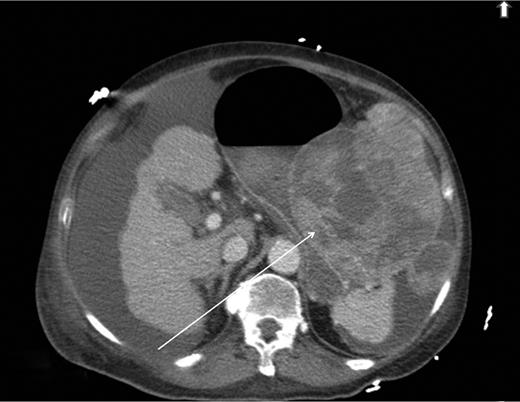

A computed tomography scan was performed which showed multifocal HCC with a large exophytic lesion invading into the greater curvature of the stomach (Figs. 3 and 4). Peritoneal metastases and ascites were present. The patient underwent an angioembolization of the hepatic tumour on the same evening. Angiography identified a replaced left hepatic artery as the dominant vessel supplying the lesion of concern in the left lateral hepatic segment (Fig. 5a). Gelfoam embolization was performed with no residual tumour enhancement thereafter (Fig. 5b).

Computed tomography image showing HCC invading into greater curvature of stomach.